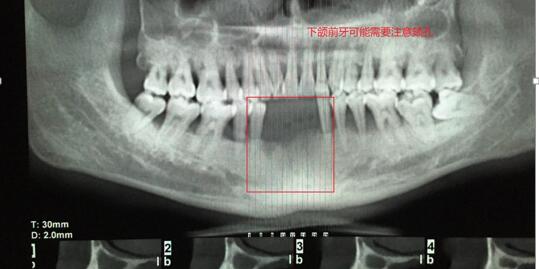

案例二:下頜前牙缺失